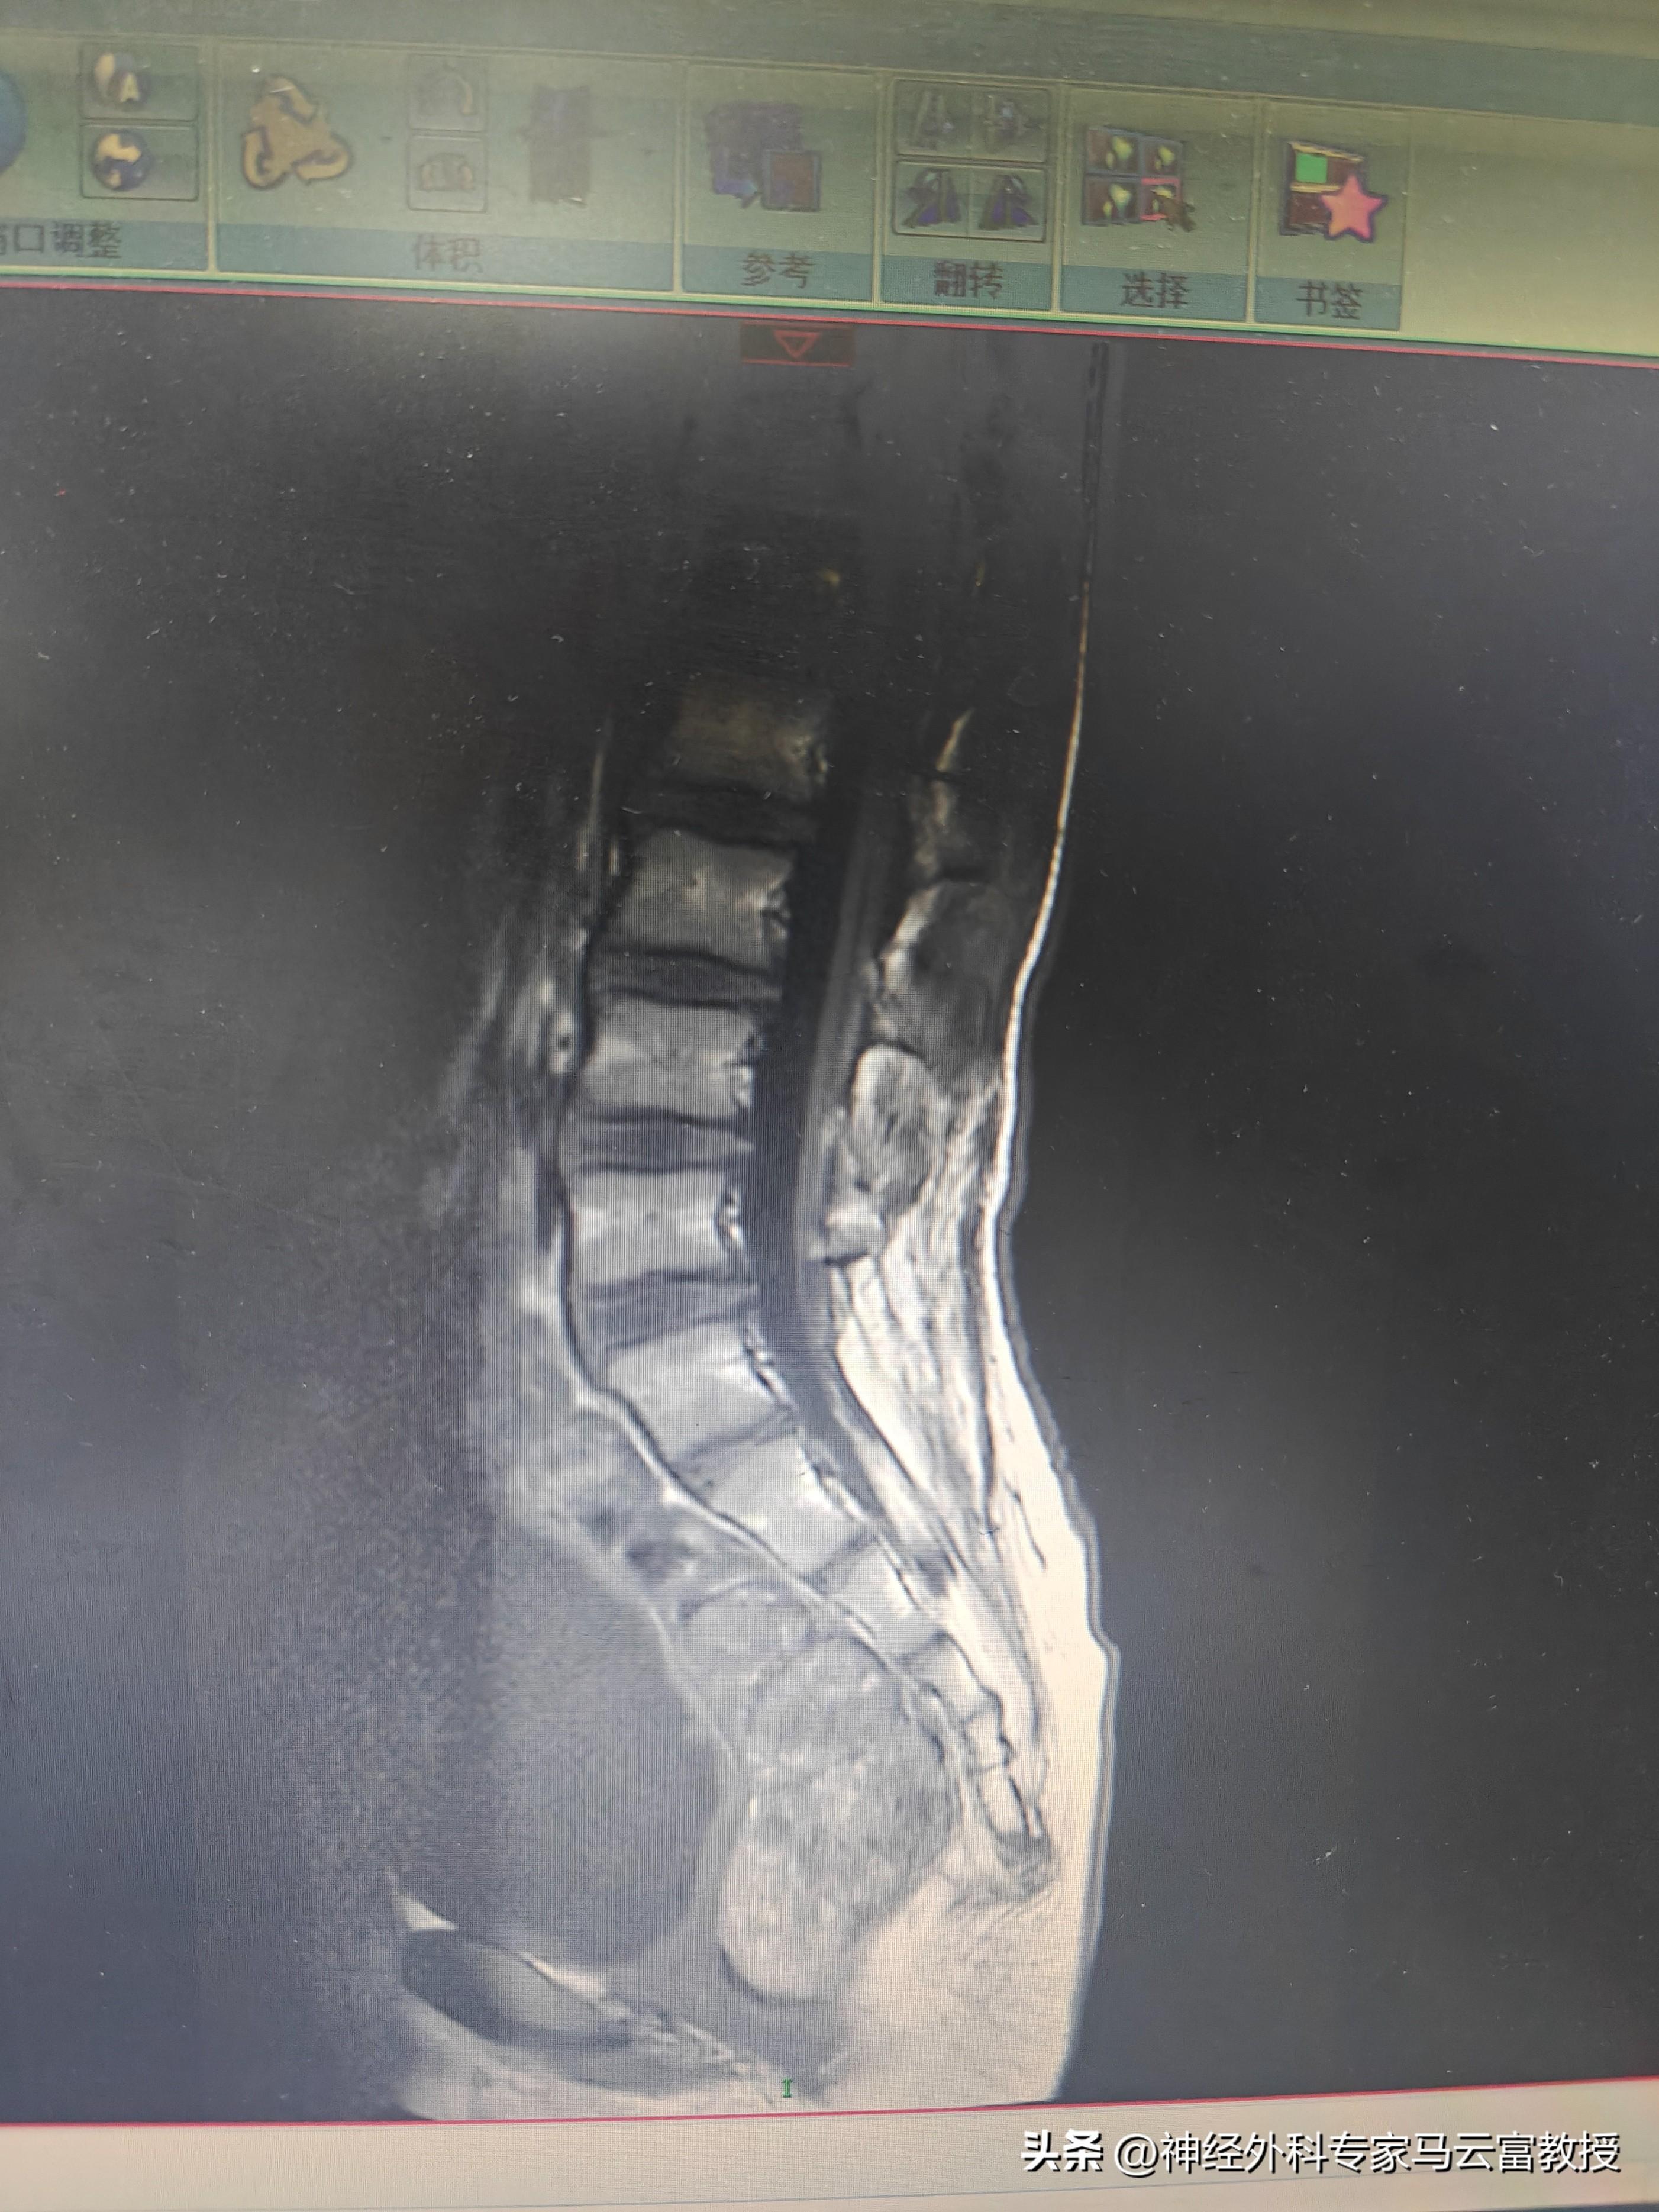

可就在近期,小李出現了頻繁尿褲子、大便乾結的異常情況,這讓家人再次陷入焦慮。懷揣着不安,他們帶着小李千里迢迢從河南趕來湖北,再次來到湖北省婦幼保健院神經外科複查,而複查結果顯示,小李椎管內出現脂肪堆積,馬尾神經增粗——這正是導致他大小便異常的根源,也意味着需要再次接受手術治療。

小李的複查MRI

小李複查的MRI